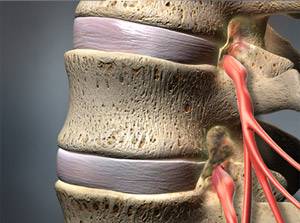

Bei einer Spinalkanalstenose handelt es sich um eine Verengung im Wirbelsäulenkanal. Sie entsteht durch degenerative Veränderungen der Wirbelkörper, die mit der alternden Wirbelsäule voranschreiten. Dadurch, dass es im Spinalkanal eng wird, haben die darin verlaufenden Nerven weniger Platz und werden komprimiert. Der ständige Druck auf das Nervengewebe führt im Verlauf der Zeit zu vielerlei Beschwerden. Typisch sind Schmerzen und Gefühlsstörungen wie Kribbeln oder Taubheit. Das Stehen und Gehen wird immer schwerer, und in ausgeprägten Fällen entwickeln sich Kraftlosigkeit und Lähmungen.

Auch eine Spondylodese (Versteifungsoperation oder Fusion) kann bei einer Spinalkanalstenose sinnvoll sein. Ist eine Überbeweglichkeit der Wirbelsäule durch Gleitwirbel (Spondylolisthesis) die Ursache der spinalen Stenose, reicht eine reine Dekompression häufig nicht aus. Nur eine Spondylodese, eine Fusion der Wirbelkörper, die das betreffende Bandscheibensegment bilden, eignet sich in diesem Fall für eine Therapie. Die Spondylodese stabilisiert die Position der Wirbelkörper zueinander dauerhaft und stoppt das einengende Wirbelgleiten. Wenn Bedarf besteht, lässt sich die Spondylodese mit einer Dekompression (operativen Weitung des Wirbelkanals) kombinieren.

In manchen Fällen reicht das Abtragen von störenden Strukturen oder eine Versteifung nicht aus, um Druck vom Nervengewebe zu nehmen. Dann sind sog. Cages eine Option. Sie werden z. B. im Rahmen einer Fusionsoperation (Spondylodese) als Platzhalter in das Bandscheibenfach zwischen zwei Wirbelkörpern eingesetzt. Dort kann der Cage aufgespreizt werden und sich einklemmen. Auf diese Weise hilft er, zwischen den Wirbelkörpern einen ausreichenden Abstand und den Druck vom Nervengewebe zu halten.